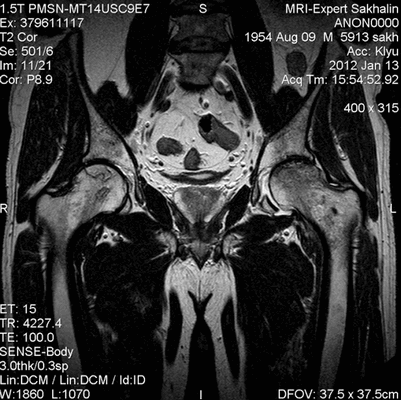

В норме на МРТ при расшифровке врач получает следующие сведения:

костная ткань однородная, отсутствуют признаки дистрофии;

равномерные суставные щели;

отсутствует субхондральный склероз суставных поверхностей;

капсула сустава не утолщена, присутствует незначительное количество синовиальной жидкости и при этом МР-сигнал от нее должен быть однородным;

связки не повреждены;

вертлужные впадины не изменена;

хрящ не истончен;

отсутствуют очаговые поражения костных структур и краевые костные заострения;

мягкие ткани не повреждены и не изменены.